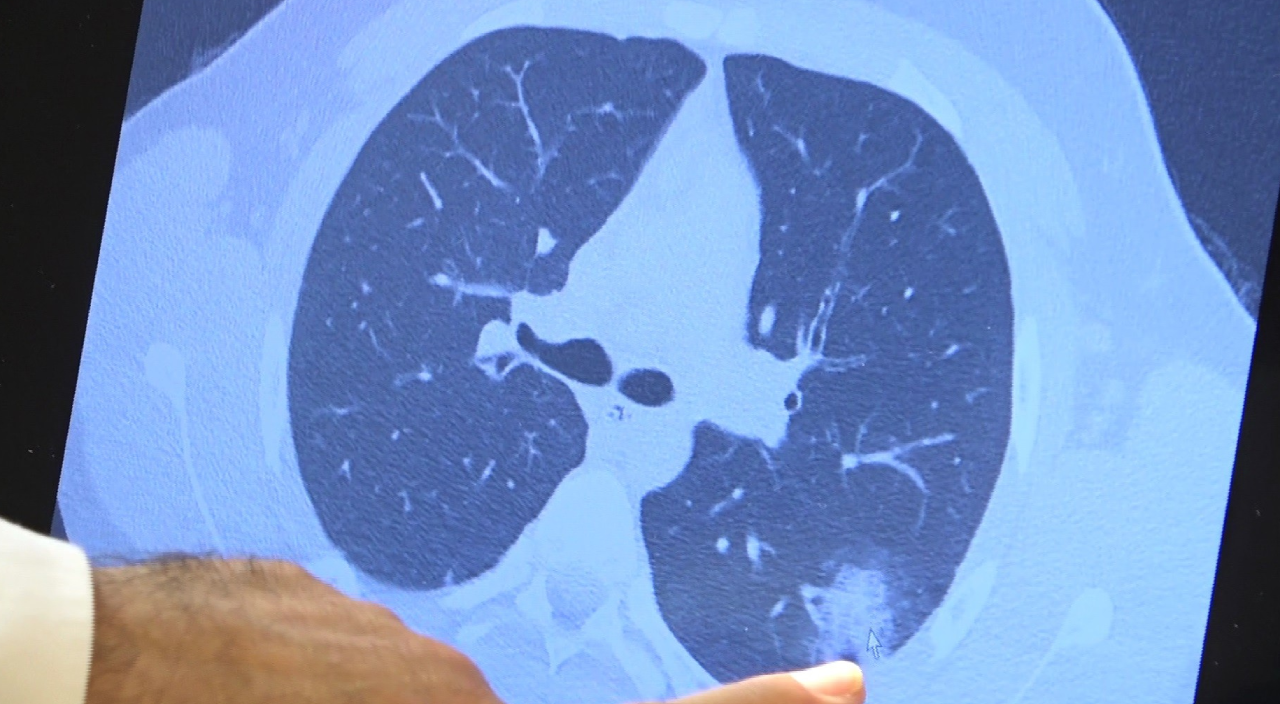

Bazı vatandaşlar hâlâ aşı olmakta tereddüt etmeye devam ederken korona virüs çocuk grubundaki hastaları da etkilemeye başladı. Prof. Dr. Şevket Özkaya ise aşı olabilecek yaş grubundaki çocukların bir an önce aşılanması gerektiğine vurgu yaptı. 14 yaşında, kronik rahatsızlığı olan ve akciğerlerinde tahribattan dolayı ciddi öksürük, ateş ve nefes darlığı çeken bir hastanın akciğerlerini inceleyen Prof. Dr. Özkaya, "14 yaşındaki kronik rahatsızlığı mevcut olan bir genç hastamızda ciddi akciğer tutulumları var. Her iki akciğerinde de yaygın buzlu cam ve konsolidasyon alanları var. Bu yaştaki çocuklarda beklemediğimiz bir durumdur. Okullarımızda da bu risk var. Okullarımızın açık kalmasının ve sağlık sistemimizin kitlenmemesi için mutlaka aşı olmalıyız. Çocuklarımıza rol model olmalıyız. Şu anda hastanelerimiz hastalara yetişebiliyor. Yatak sayımız yeterli. Ancak kontrollü sosyal hayatımızı düzene sokmadıkça ve aşı olmadıkça, gelecekte hastanelerde yatak sayısı sıkıntısı çekebiliriz" dedi.